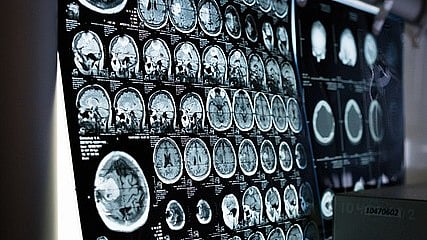

3 மடங்கு துல்லியம்... பிரான்ஸில் கண்டறியப்பட்டுள்ள `வேற மாதிரி' MRI scan கருவி! 🕑 Fri, 05 Apr 2024

3 மடங்கு துல்லியம்... பிரான்ஸில் கண்டறியப்பட்டுள்ள `வேற மாதிரி' MRI scan கருவி!

அதிக துல்லியமான MRI கருவி:உலகில் முதன்முறையாக மனித மூளையில் உள்ள நுண்ணுறுப்புகளின் செயல்பாடுகளைக்கூட காட்சிப்படுத்தும் அதிகாந்த சக்தி வாய்ந்த